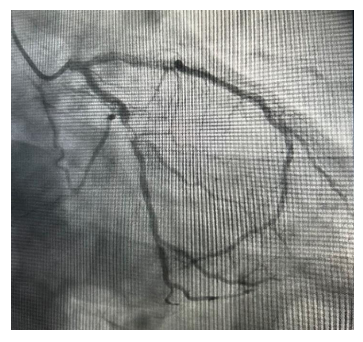

Um paciente de 71 anos, com história prévia de hipertensão arterial, dislipidemia e doença arterial coronariana com angioplastia, é trazido à emergência após episódio de síncope precedida por dor precordial durante partida de tênis.

O eletrocardiograma da admissão mostra a seguinte imagem:

É encaminhado para a sala de hemodinâmica, onde se encontra a imagem a seguir.

O diagnóstico do paciente e a artéria acometida são, respectivamente: